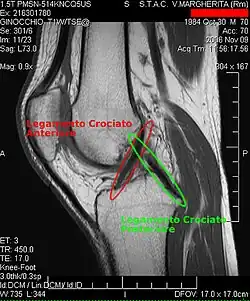

Bildgebende Verfahren

Die Diagnose kann mit bildgebenden Verfahren – namentlich der Magnetresonanztomographie (MRT, „Kernspin“) – bestätigt werden. Dabei ist allerdings zu beachten, dass die Interpretation der MRT in der Diagnostik eines Kreuzbandrisses zu 20 Prozent falsche Diagnosen liefert. Hier kommt es auf die sogenannten Schnittbilder und die geeignete Positionierung des Kniegelenkes bei der MRT-Untersuchung an. Der Radiologe sollte die genaue Vorgeschichte kennen, die zur Verletzung führte, und auch Erfahrung in der Untersuchung eines verletzten Gelenkes haben, um Fehlbeurteilungen zu vermeiden. Im Vergleich zur MRT liegt die Fehlerquote bei dem erheblich einfacher durchzuführenden Lachman-Test bei nur 10 Prozent.[85][86][87][88] Die MRT ist daher in der Regel zur Diagnose eines vorderen Kreuzbandrisses weniger sensitiv und weniger spezifisch als die klinische Befundung durch einen qualifizierten Orthopäden.[89] Das Ergebnis einer MRT hat nur relativ selten einen Einfluss auf die klinische Entscheidungsfindung[90] und sollte keinen Ersatz für eine sorgfältige Anamnese und Palpation darstellen.[15] Mehrere Studien kommen zu dem Schluss, dass eine MRT nur bei komplizierteren unklaren Knieverletzungen – und dabei eher zum Erstellen einer Ausschlussdiagnose[91] – sinnvoll ist.[92][93]

Röntgenaufnahmen leisten keinen unmittelbaren Beitrag zur Diagnosestellung einer Kreuzbandruptur. Beide Kreuzbänder sind – ob gerissen oder nicht – im Röntgenbild nicht sichtbar. Wird dennoch geröntgt, so kann dies der Diagnosestellung von möglichen knöchernen Begleitverletzungen dienen.